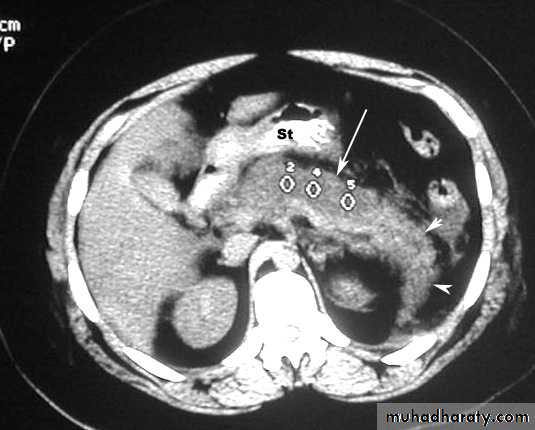

Acute Pancreatitis

CT used to

• 1. Pancreatic necrosis .• 2. An abscess.

• 3. Vascular complications.

• 4. Pseudocyst

1

3

2

4